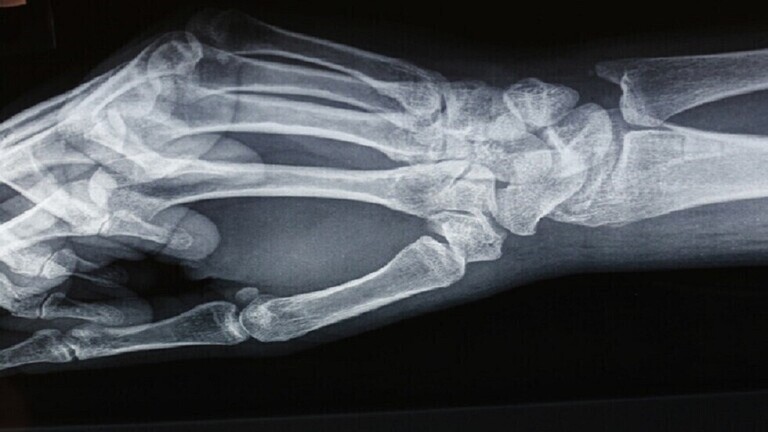

ومقارنة بالأشخاص الذين تناولوا اللحوم والأسماك، وجد العلماء أن أولئك الذين يتناولون كميات أقل من الكالسيوم والبروتين كانوا أكثر عرضة لكسور الورك والساق والعمود الفقري.

وكان النباتيون أيضا أكثر عرضة بنسبة 43% للإصابة بكسور في أي مكان. وهذا ينطبق بشكل خاص على الساق والفقرات وعظم الترقوة.

ووجد البحث أن النباتيين أكثر عرضة للإصابة بالكسور الكلية ما أدى إلى ما يقرب من 20 حالة أخرى لكل 1000 شخص خلال فترة 10 سنوات مقارنة بالأشخاص الذين تناولوا اللحوم. ووجدت الدراسة أن الاختلافات الأكبر كانت في حالات كسور الورك حيث كان الخطر لدى النباتيين أكثر من ضعفي أولئك الذين تناولوا اللحوم.